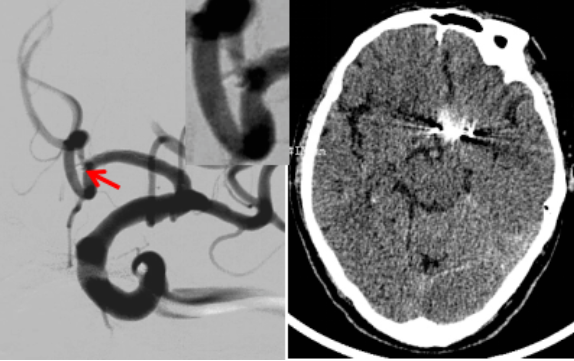

由于血管迂曲,术中运用了中间导管技术顺利建立手术通道,该动脉瘤为宽颈动脉瘤,术中使用了支架辅助栓塞技术进行治疗(图3)。该动脉瘤瘤体薄如蝉翼,术中每一个细微的动作都惊心动魄,扎实的显微操作基础及娴熟的介入手术技巧使手术得以顺利完成,术后患者意识好转、言语功能恢复,自主生活能力得到了明显改善。

(图3 术后DSA造影及术后头颅CT)